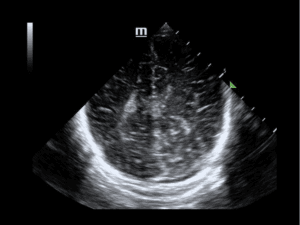

Case 5

A 9-year-old male with a history of Celiac disease presented with hours of abdominal pain that migrated to the RLQ. He denied fever, vomiting and diarrhea. VAS was 4. Examination was significant for right upper and lower abdominal tenderness with positive Rovsing and obturator signs. CBC was unremarkable, CRP 2.37 mg/dL. POCUS showed enlarged mesenteric lymph nodes in the right lower quadrant of the abdomen, with a 7-millimeter noncompressible appendix (Figure 7, Video S1). He was admitted for observation. On hospital day 1 CBC was again unremarkable, CRP 2.27 mg/dL. RADUS found a 6-millimeter appendix partially compressible with surrounding inflamed fat, “possibly consistent with early appendicitis.” Repeat RADUS on hospital day 2 was unchanged. On both hospital days, examination by the attending gastroenterologist showed a soft abdomen with mild right lower quadrant tenderness. Examination by the attending surgeon was similar and deemed inconsistent with acute appendicitis, and the patient was discharged home.

Figure 7. 7-millimeter appendix with wall thickening in long-axis.

Video S1. 7-millimeter appendix with wall thickening in long-axis.